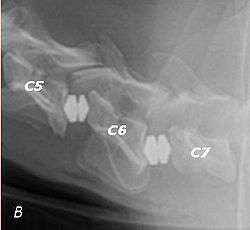

T2 weighted MRI in neutral (A) and linear traction (B) of a seven-year-old Doberman with a two-year history of cervical pain treated with NSAIDs and presented acutely tretraplegic: A C6-C7 and C5-C6 traction responsive myelopathy are evident on MRI. The spinal-cord hyperintensity seen at the C5-C6 is suggestive of chronic lesion and most likely responsible for the chronic history of cervical pain, while the C5-C6 lesion was most likely responsible for the acute tetraplegia.

Same dog (A) treated with double implant (B) three days after surgery: The dog became ambulatory three days after surgery. Four weeks after surgery, it had ataxia without conscious proprioceptive deficits, and three months after surgery, the dog was neurologically normal. The owner reported it had been two years since the dog was able to hold its neck in an elevated position.